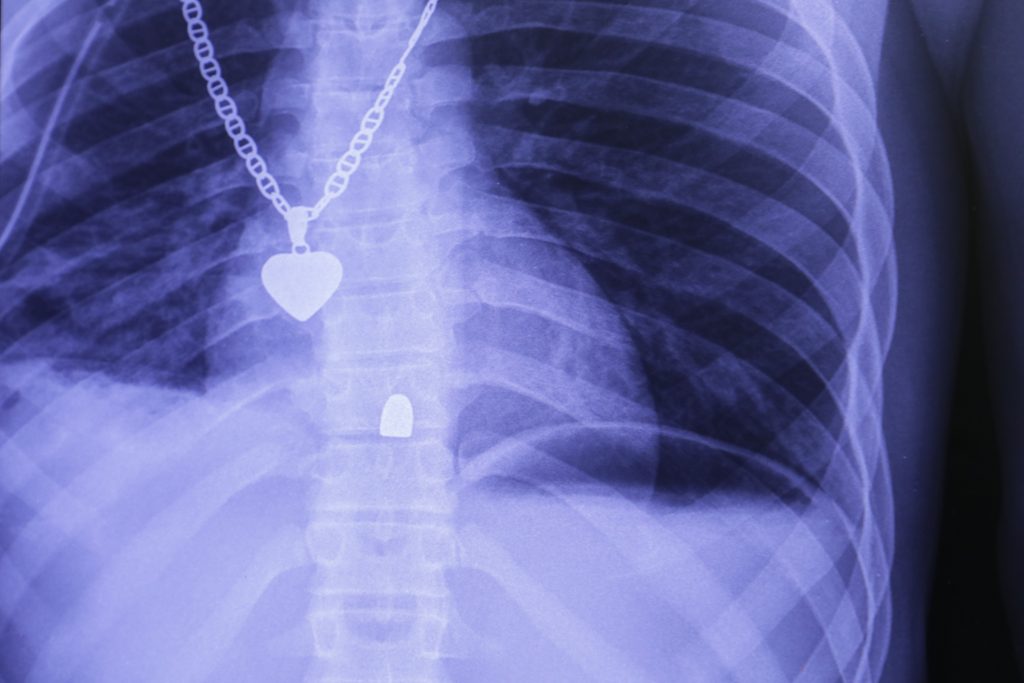

An X-ray taken at MSF’s emergency trauma hospital in the Tabarre area of Port-au-Prince. A bullet is lodged in the patient’s spine. Haiti, December 2019.

NICOLAS GUYONNET/MSF